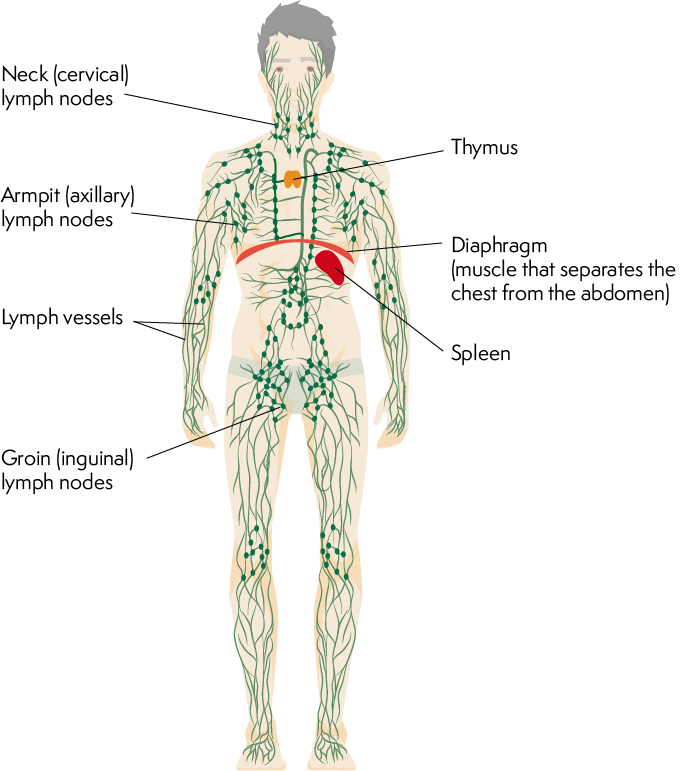

Lymph Node Locations And The Importance Of Lymphatic Drainage

blossomingwidow.com

blossomingwidow.com

lymphatic lymph system node drainage locations does do

Lymph Nodes 101

www.iheartpathology.net

www.iheartpathology.net

lymph nodes body node glands located lymphatic part they throughout small